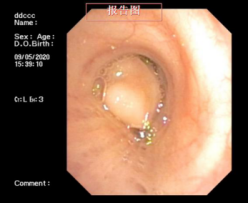

近日,一位患支氣管腫瘤患者到我院呼吸內科治療,檢查時,其腫瘤幾乎已經完全堵塞氣管管腔,若不及時手術,隨時可能發生呼吸衰竭。

情況危急,醫生立即為其抽取動脈血化驗并給予高流量吸氧等,但患者呼吸困難的癥狀緩解不明顯,必須及時將腫瘤切除。“如果按照傳統的手術方式,需將患者氣管切開,組織損傷性高、流血量多。由于患者腫瘤貼近降主動脈,切除過程中將伴有大出血的風險。”劉碧翠說,隨著我院內鏡技術的發展,對于這樣的重癥患者,可以利用呼吸內鏡迅速切除腫瘤,清理氣道內局部的壞死組織、分泌物并予以止血處理。

科室介入團隊經過精心準備后,立刻為患者實施內鏡介入手術,將氣道內腫物切除干凈。手術僅用時2小時,患者沒有發生大出血,很快便恢復出院。此次手術的成功開展,充分體現了呼吸內科對此類疑難危重氣道疾病患者的救治能力。